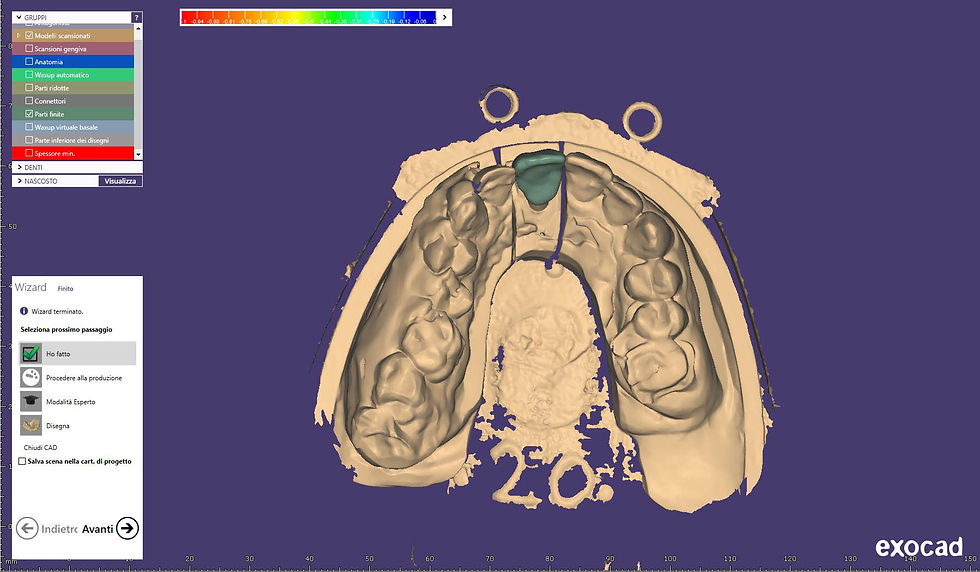

CAD-CAM design of the definitive crown.